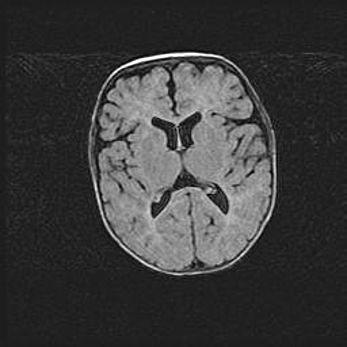

Лейкомаляция с кистозно-глиозной дегенерацией головного мозга.

Возраст: 2 месяца 25 дней

Вес: 6400 г

Окружность головы: 40 см

Срок гестации: 41 неделя

Лейкомаляцию относят к ишемически-гипоксическим повреждениям головного мозга, диагностируемым у новорожденных. При лейкомаляции в головном мозге обнаруживают очаги некроза, возникшие после тяжелой гипоксии и нарушения кровотока. В процессе морфогенеза очаги проходят три стадии: 1) развития некроза, 2) резорбции и 3) формирования глиозного рубца или кисты. Перивентрикулярная лейкомаляция (ПЛ) встречается примерно в 12% случаев среди новорожденных, обычно – у недоношенных детей, причем, частота ее зависит от массы, с которой младенец появился на свет. Наибольшее число малышей страдает лейкомаляцией, если масса при рождении 1500-2500 г.